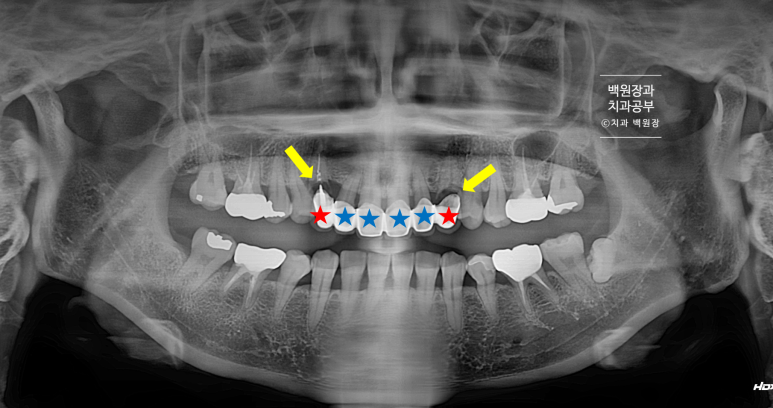

같은 사진입니다. 빨간색과 파란색 별로 치아를 표시해두었는데요, 별이 붙은 6개의 치아가 하나의 보철물로 묶여서 제작되어 있었습니다. 그로 인해 치실을 잘 사용할 수 없음이 이차 충치로 이어지게 된 원인으로 작용했죠.

빨간색으로 표시된 양쪽의 두 송곳니의 뿌리에 이차충치가 있었습니다.

파노라마 엑스레이에서 확실히 확인할 수 있는데요,

똑같이 6개의 앞니를 별로 표시해 보았습니다.

빨간색으로 표시한 두 개의 송곳니 모두 치근우식이 있는 것을 관찰할 수 있습니다. 뿌리에 충치가 심했어요.

노란색 화살표로 가리킨 곳에 파노라마 엑스레이상 소견으로 까맣게 충치가 생겨있는 것을 볼 수 있죠.